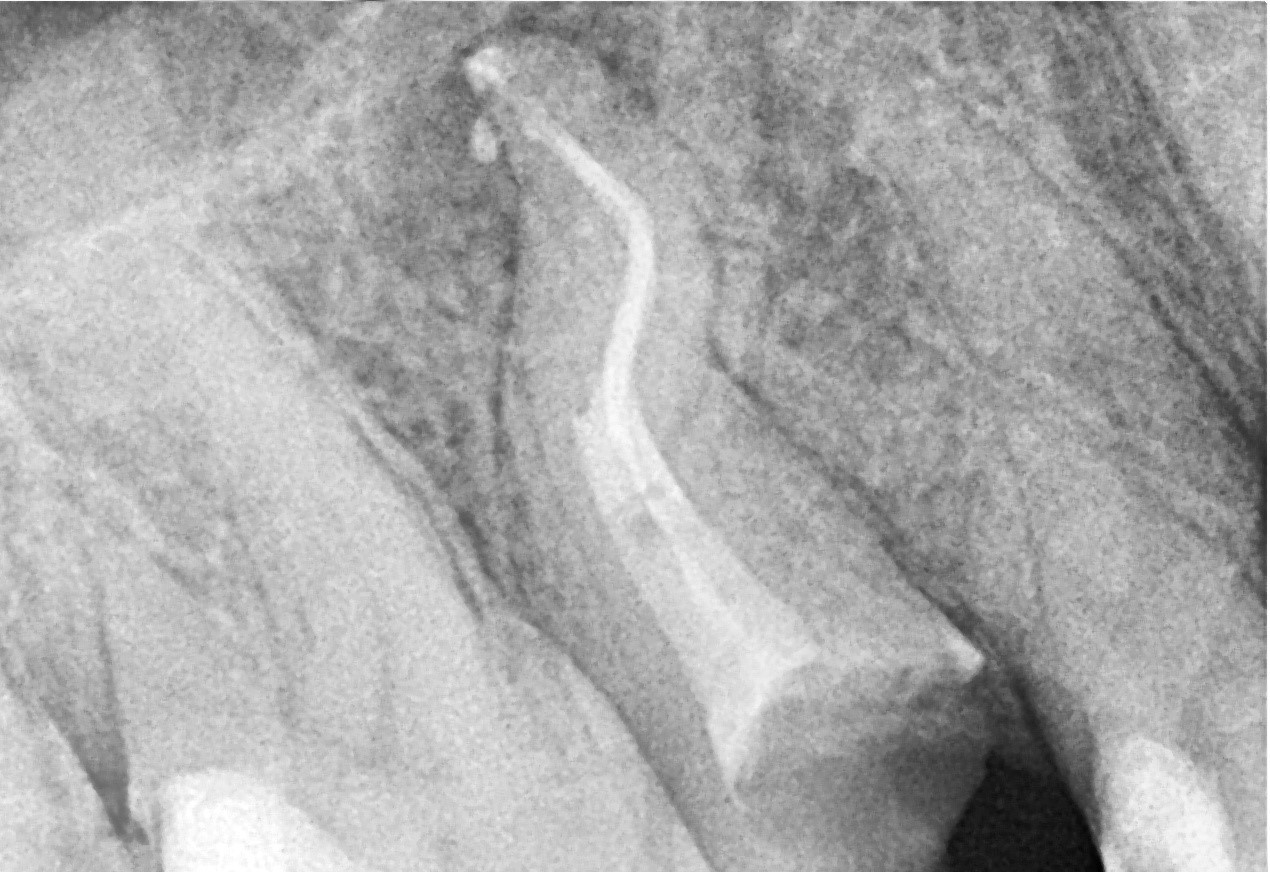

• In the palatal canal, the 10/07 “Opener” file from the SuperSystem Advanced Kit was used at 250 rpm and 1.5 Ncm torque, progressing to the middle third.

Following irrigation, 17/05 file was used at the same settings to reach the apex.

Working length was confirmed using a #06 K-file.

Canal enlargement was completed with the Perfect Advanced Kit 17/05 file (images 3 and 4).